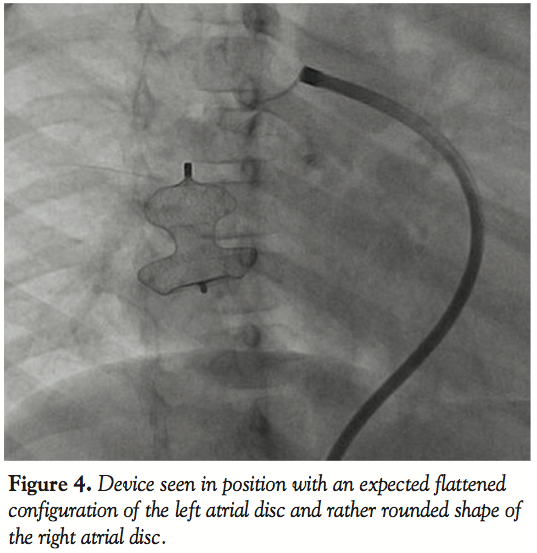

single and the narrow segment measured 14 mm with the proximal portion measuring 26 mm. Considering the morphology of the fistula, we decided to close the defect antegradely. As the fistula was large and roomy we decided to close the feeding vessel with an atrial septal occluder. The left atrial disc would easily be accommodated in the aneurysmal sac and the right atrial disc was expected to configure into the shape of the feeding artery without protruding into the lumen of RPA. The constricted segment was well away from the branches of the RPA as well as the opening of the pulmonary veins into the left atrium. The balloon was removed and an 8 Fr long Cook sheath was introduced antegradely over the Amplatz wire through RPA, across the fistula into the LA. As the constricted segment measured 14 mm, we deployed a 16 mm Cardiofix atrial septal occluder (Starway Medical Corporation) across the narrow portion of the feeding vessel. While the left atrial disc assumed the expected shape, the right atrial disc was rounded due to comparatively less space in the feeding artery. We did RPA injections in multiple views to be sure that there was no obstruction to RPA flow as well as that there is no residual flow across the fistula (Figure 3, Video 3). After checking the stability of the device, it was released (Figure 4, Video 4). The patient’s saturation improved to 100% and there was no residual fistula on follow-up. He was put on oral aspirin for 6 months and is doing well on follow-up without any complications.